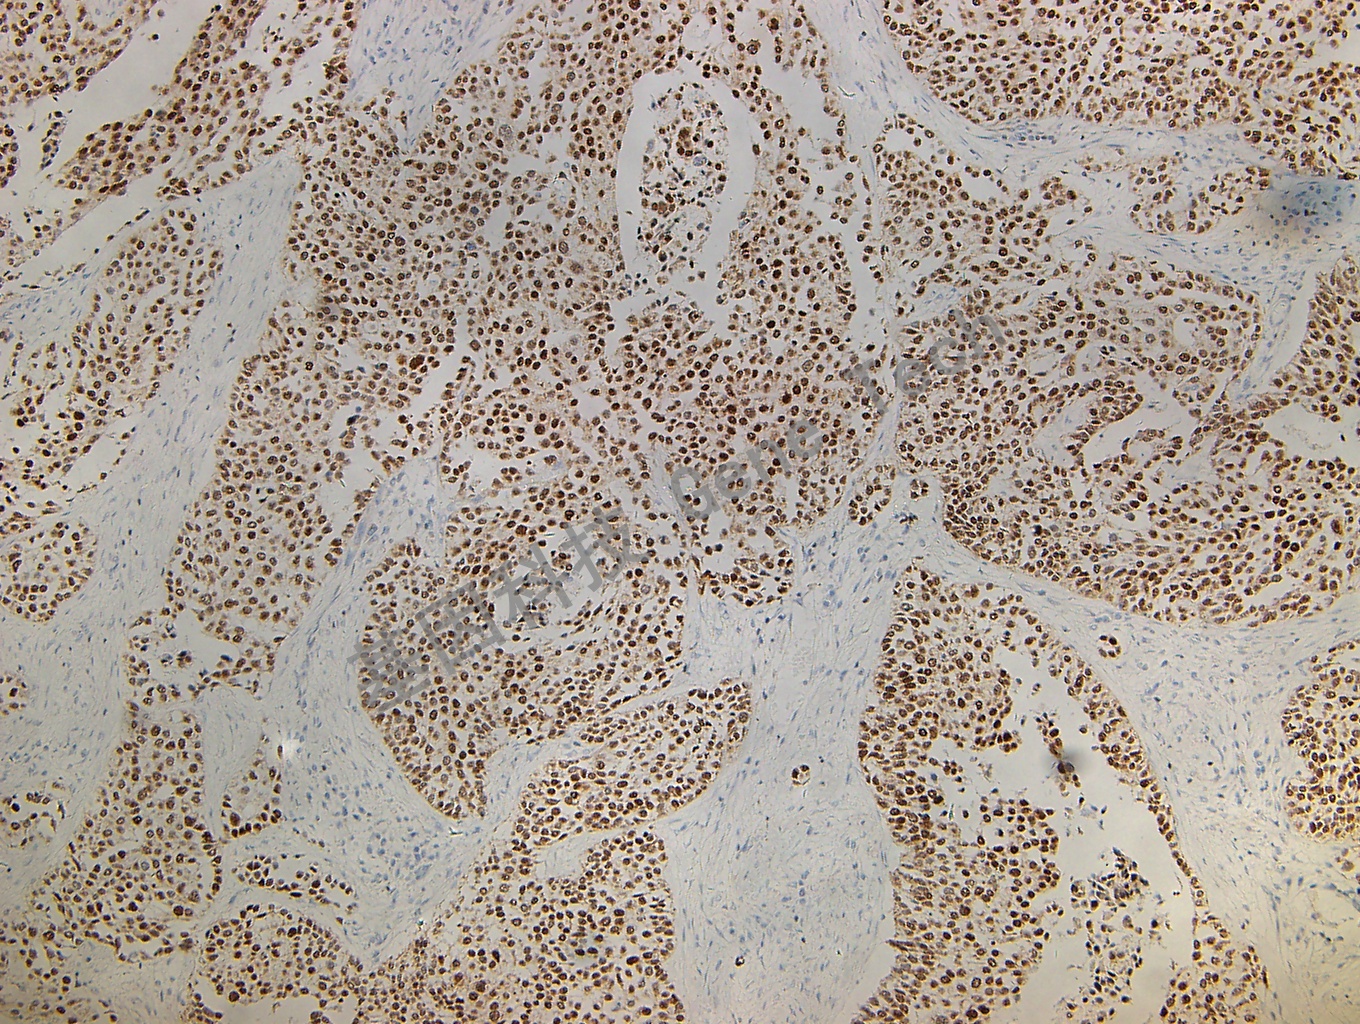

尿路上皮癌石蜡切片,用 GATA3(GT2187)染色,细胞核阳性,DAB 显色。